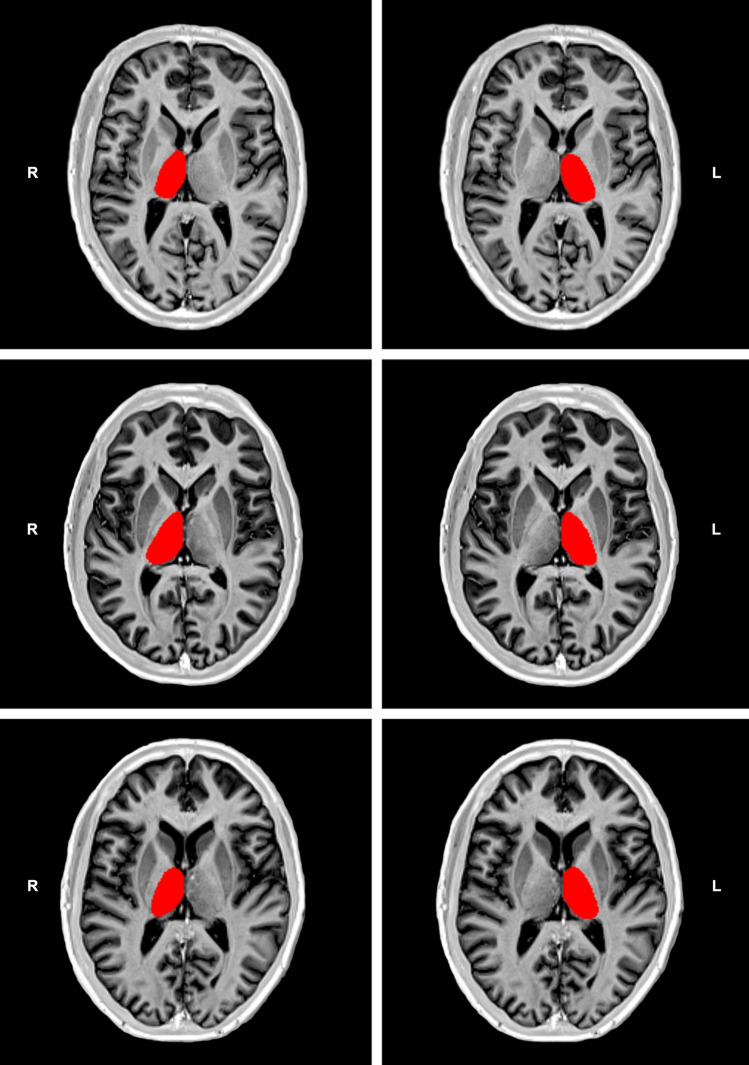

We applied a validated manual segmentation protocol12 using the MRIcron software (https://www.nitrc.org/projects/mricron) on bias-corrected 2D IR TSE T1-WI. Although the implementation of a manual segmentation procedure on axial T1-WI implicated a very slight adaptation of the original protocol, it is noteworthy to point out that the reliability analysis of such a protocol has shown that the corresponding intra-class correlation coefficient ranged from 0.95 to 0.98, and the inter-class correlation coefficient ranged from 0.92 to 0.9812. Figure 1 shows examples of the thalamic segmentation procedure implemented in the current study. To obtain accurate thalamic volumes, all images including the thalamus were cautiously selected. Care was taken to exclude the metathalamus, epithalamus, subthalamus, hypothalamus, and the choroidal plexuses from measurements. The segmentation procedure was carried out by two observers (A.J. B.-L. and J.J.R.), the more experienced of which (with approximately 2 decades of experience in diagnostic neuroradiology) supervising the other. We also used visual rating scales to assess medial temporal lobe atrophy (MTA)23 and global cortical atrophy (GCA)24 scores on 3D MPRAGE T1-WI in consensus by two observers (S.B. and A.J. B.-L.). At the time of each assessment, all observers were blinded to the clinical characteristics of the included patients.

Figure 1.

Examples of thalamic segmentation on bias corrected inversion recovery (IR) turbo spin echo (TSE) T1-weighted images (T1-WI) from one patient with nonpainful diabetic peripheral neuropathy (DPN) in the top row and one patient with painful DPN in the middle row. In the bottom row, an example of a similar segmentation procedure on a 46-year-old healthy subject is shown. This example is presented for visualization purposes only, and was randomly selected from a sample of a previous study using similar IR TSE T1-WI to segment deep gray matter structures11. Please note the apparent reduction of thalamic volume (especially the thinner cross-sectional thalamic distance) in the patient with nonpainful DPN, especially in the right thalamus, relative to the other examples.

Our study showed that the average left–right thalamic volume was 5492 mm3 in patients with type 1 DM and DPN, 5072 mm3 in patients with nonpainful DPN, and 5976 mm3 in patients with painful DPN. Taking as a reference the results of a previous study reporting thalamic volumes in healthy subjects by using a similar segmentation method12, our data suggest that thalamic volumes in patients with type 1 DM and nonpainful DPN are substantially lower than those of healthy subjects (Fig. 1). This is consistent with results of a recently published study10. Nevertheless, the corresponding proportion of volume reduction should be confirmed in future studies including healthy control subjects. It is, however, noteworthy to point out that thalamic volumes calculated on the basis of automatic segmentation methods or stereology have always indicated values > 7300 mm3 in healthy young adults28,29.